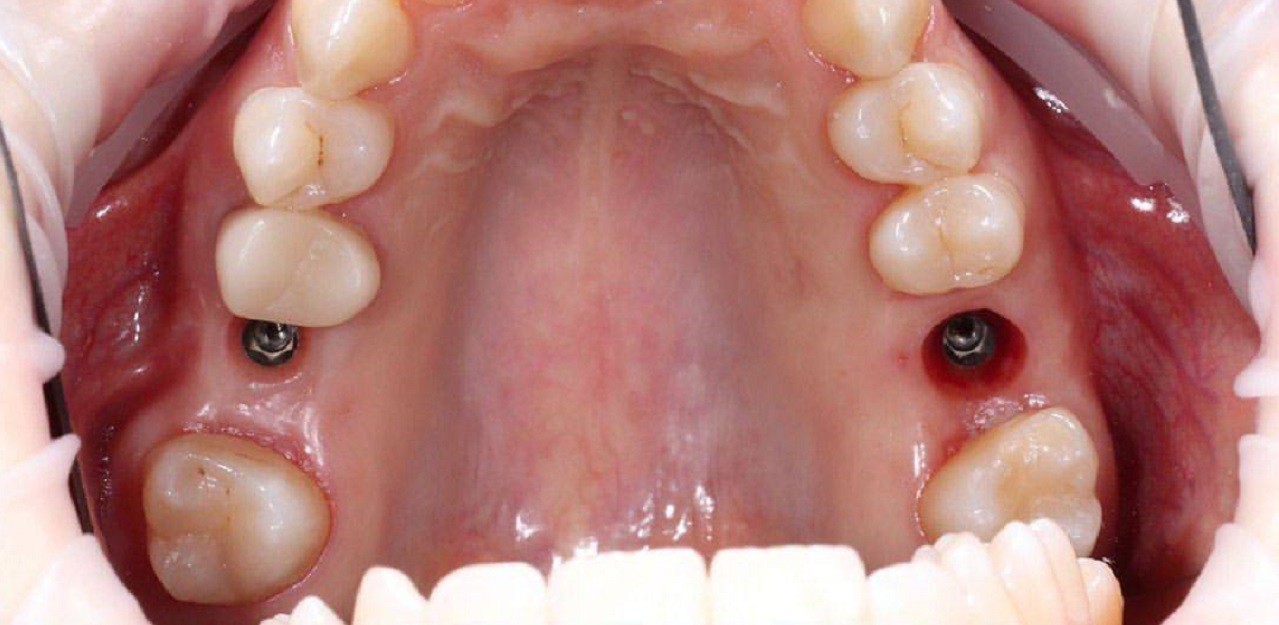

Пациент 55 лет.

Жалобы на невозможность полноценного пережевывания пищи, дефект дикции, отсутствие эстетики.

Диагноз: частичная вторичная адентия, генерализированный пародонтит на в.ч и н.ч

Жалобы на невозможность полноценного пережевывания пищи, дефект дикции, отсутствие эстетики.

Диагноз: частичная вторичная адентия, генерализированный пародонтит на в.ч и н.ч